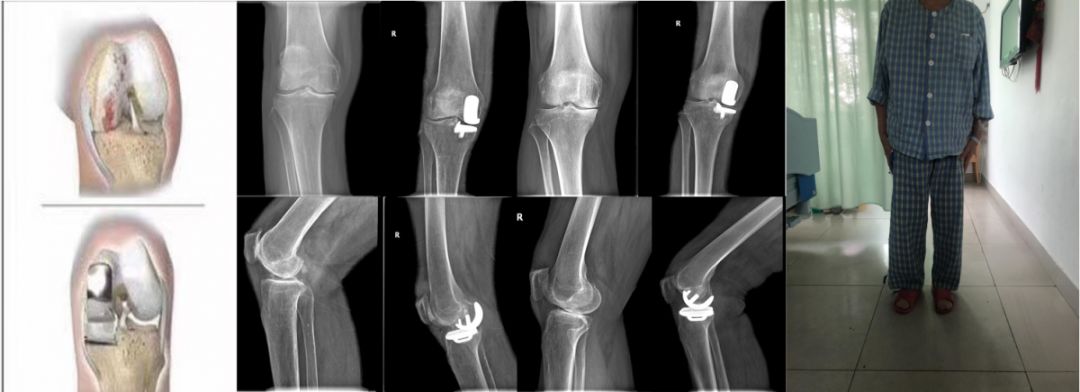

而后,彭女士在社区科普讲座上,听到南方医科大学中西医结合医院骨伤科黄刚主任说膝骨关节炎能够进行微创手术,于是慕名前来就诊。入院后,我院骨伤科主任黄刚经过仔细查体,结合相关辅助检查后,制定了“膝关节单髁置换”手术方案,术后彭女士膝关节疼痛基本缓解,术后第二天已经可以下地正常行走。

黄刚主任表示,彭女士是膝关节其中一个间室的软骨磨损,所以才会出现行走畸形、疼痛难忍,严重影响了生活质量。当保守治疗无效时,只有将损坏的软骨重新用“高科技组合”进行替换,恢复崭新的关节间室。“高科技组合”主要有这几种:

2、单髁置换术,就像是牙坏了一部分,只需要把坏的部分修理好,类似补牙。

而彭女士做的单髁置换手术,体现了微创理念,具有恢复快,住院时间短,住院成本比较低等优势。术中操作相对更精细,去的骨量相对少,切口更小,术中出血少,做完手术以后感染率降低。

单髁手术完整保留了对侧半月板、前后交叉韧带,患者本体感觉保留比较好,在人行走或运动中,对自己的外知觉、力量大小、体位变化能进一步感觉到,很多患者做完手术都忘记自己做过手术。